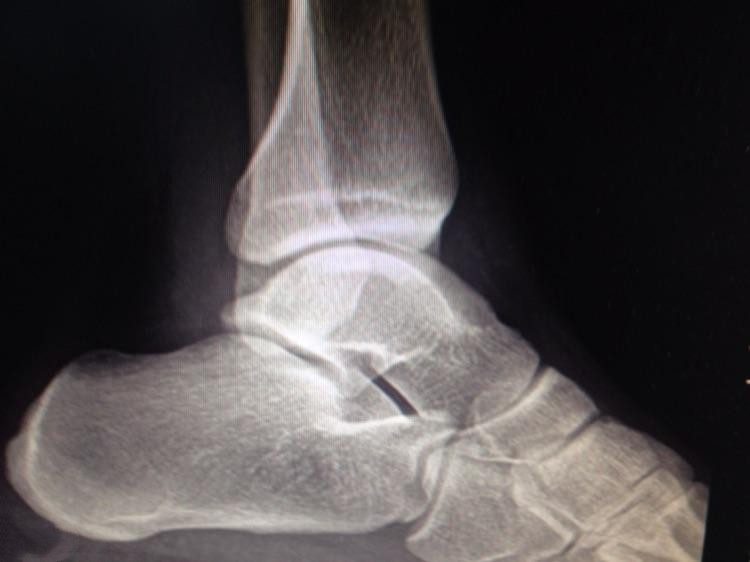

踝关节由胫骨、腓骨的下端与距骨滑车构成,近似单轴的屈关节。

踝关节由胫、腓骨的下端和距骨的滑车构成。胫骨的下关节面及其内踝和后踝与腓骨的外踝共同构成一关节窝,称为踝穴。距骨的滑车嵌合在踝穴当中,在关节的周围有很多的韧带及软组织加固,使得该关节有着独特的结构及运动形式。